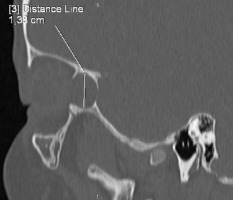

For further evaluation, the patient was referred to the Department of Pediatric Hematology and Oncology at Karol Jonscher Clinical Hospital in Poznan with a diagnosis of iritis and a suspected orbital tumor . A contrast-enhanced magnetic resonance imaging (MRI) scan of the craniofacial region was performed, revealing a well-circumscribed, slightly heterogeneous tumor mass measuring 12 × 11 × 15 mm within the right orbital boundaries, in the area of the greater wing of the sphenoid bone. The lesion demonstrated no post-contrast enhancement and showed no diffusion restriction on DWI/ADC sequences (Figure 3). Orbital computed tomography (CT) revealed bone thinning likely caused by the tumor mass, along with segmental disruption of the orbital walls adjacent to the lesion (Figure 4). The radiological findings raised suspicion of malignancy, leading to a planned biopsy. However, intraoperatively, the tumor’s well-defined margins prompted a decision to proceed with complete tumor resection with the capsule. The subsequent histopathology examination confirmed the diagnosis of DC. Symptomatic treatment for right eye uveitis was continued.